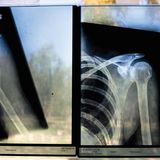

Röntgenaufnahmen

Das Korsett musste sie als Heranwachsende tragen